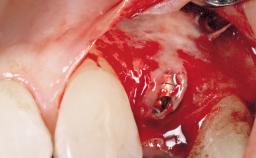

Late Flapless Placement of an Implant in a Maxillary Left Central Incisor Site

A 39-year-old male patient presented with a chief complaint of discomfort and gingival discoloration around his maxillary left central incisor. He was in good general health and was a non-smoker. His past dental history was significant because of the traumatic fracture of tooth 21 in a sporting accident at age 13. Initial dental treatment included endodontic therapy and a full-coverage restoration. The patient became symptomatic 5 years later, when structural failure of the tooth resulted in the dislodgment of the crown. Endodontic retreatment, apical surgery, and post-and-core restoration were performed.

Type of Implants One-Piece

Bone Augmentation Horizontal|Staged

Augmentation Materials Xenogenous|Membrane

Bone Volume Deficient horizontally, requiring prior grafting